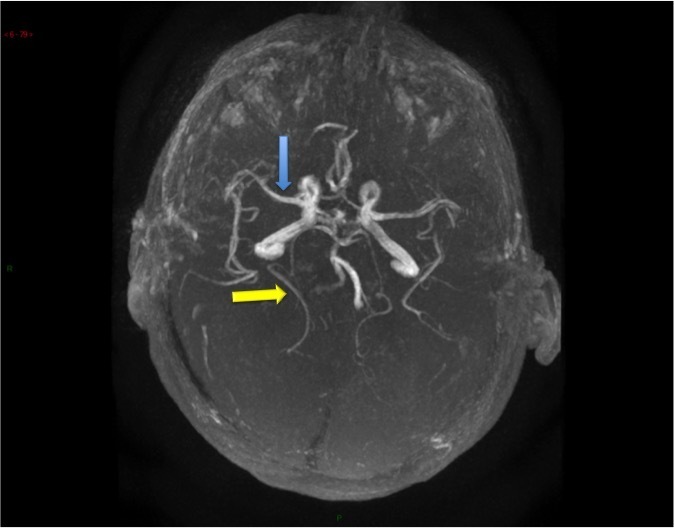

Voici l’angiographie par résonance magnétique (ARM) du polygone de Willis réalisée chez ce patient.

Question 4 : Concernant les structures légendées, quelles sont la/les proposition(s) exacte(s) ?

Artère cérébrale moyenne également appelée artère sylvienne.

Artère cérébrale antérieure gauche, naissant (hors variante anatomique) de la terminaison de la carotide interne homolatérale. Les deux artères cérébrales antérieures communiquent par une artère communicante antérieure dont la naissance est située à l’union de leurs deux premiers segments.

Artère cérébrale postérieure droite. Celles naissent du tronc basilaire communiquent avec le système carotidien via les artères communicantes postérieures (une de chaque côté).

Tronc basilaire, formé par l’union des deux artères vertébrales en intracrânien

Artère carotide interne gauche. La division de l’artère carotide commune en artère carotide interne et externe est située en extracrânien à hauteur de C4.

À noter que le polygone de Willis peut présenter de nombreuses variantes anatomiques qui peuvent avoir une répercussion en cas de pathologie artérielle (présence ou absence de suppléance via les anastomoses entre les systèmes carotidiens d’une part, carotidien et vertébro-basilaire d’autre part).